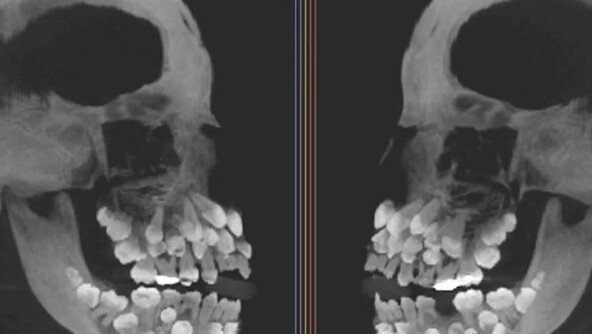

의총협 “복귀 의대생, 2학기에 1년치 수업 모두 들어야”